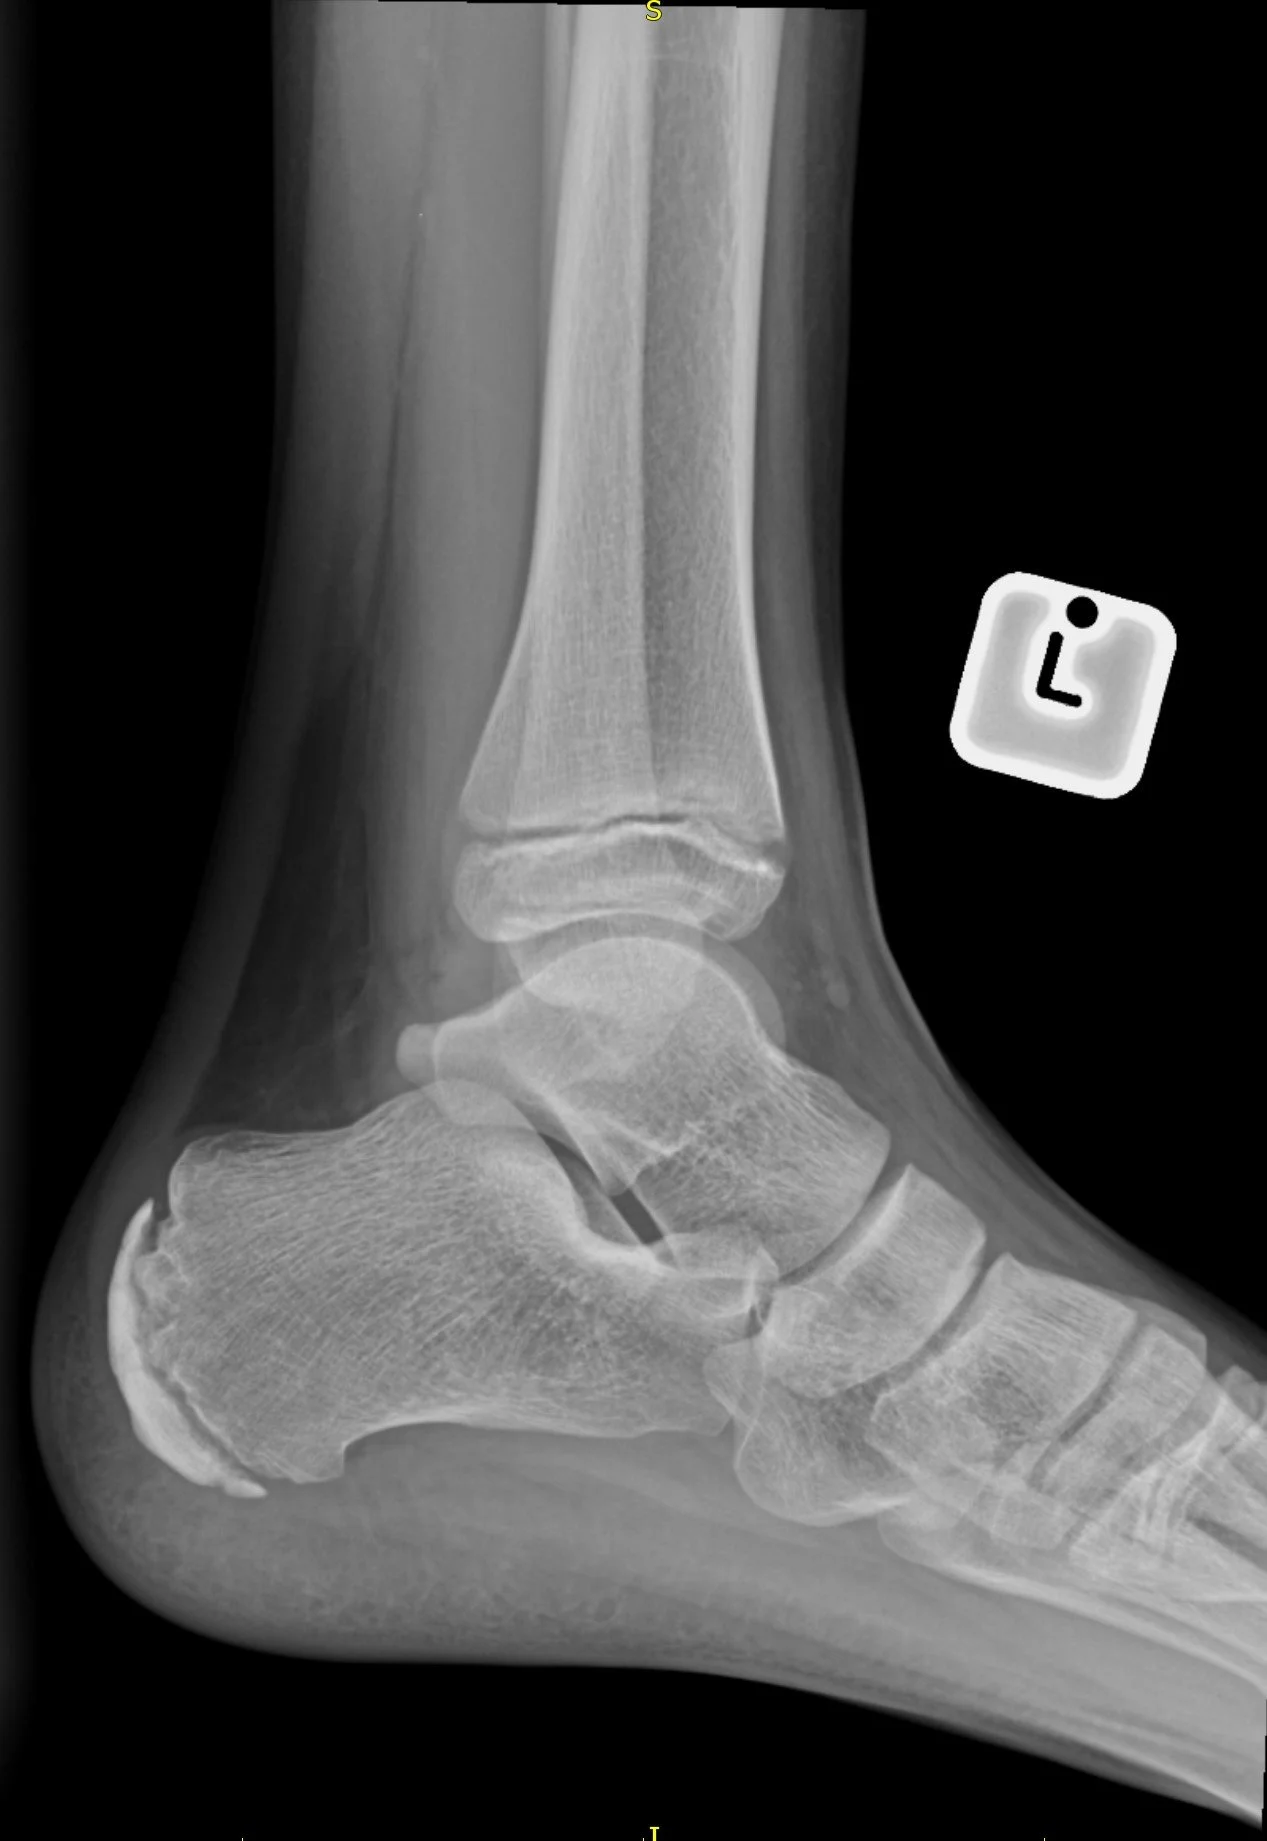

Sever Disease

• Calcaneal apophysitis

• Cause of heel pain aggravated with use commonly in kids

• Case courtesy of Ashesh Ishwarlal Ranchod, Radiopaedia.org, rID: 168346 (Sever disease)